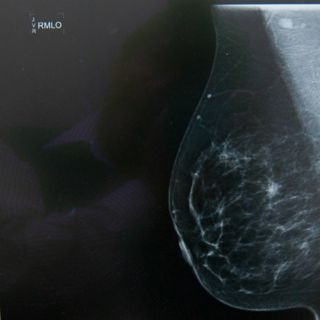

CIUDAD DE MÉXICO (22/OCT/2015).- Un grupo de jóvenes mexicanos trabaja en el desarrollo de una aplicación para

dispositivos móviles como celulares, tabletas y computadoras, que analizará las imágenes termográficas y los datos clínicos para detectar el cáncer de mama.

La aplicación denominada Thermy consistirá en un software conformado por datos clínicos y estadísticos con el uso de inteligencia artificial, la cual se complementará con una cámara termográfica que registrará el calor de la piel.

La implementación de este tipo de cámara se debe a que cuando las células cancerígenas se multiplican y crecen, el flujo sanguíneo y el metabolismo aumentan, lo que provoca un incremento en la temperatura de la piel.

Si bien, Thermy será una alternativa de detección oportuna porque analizará imágenes termográficas y datos clínicos mediante las técnicas de visión e inteligencia artificial, el ingeniero aclaró que no suple a la mastografía ni la vigilancia médica.